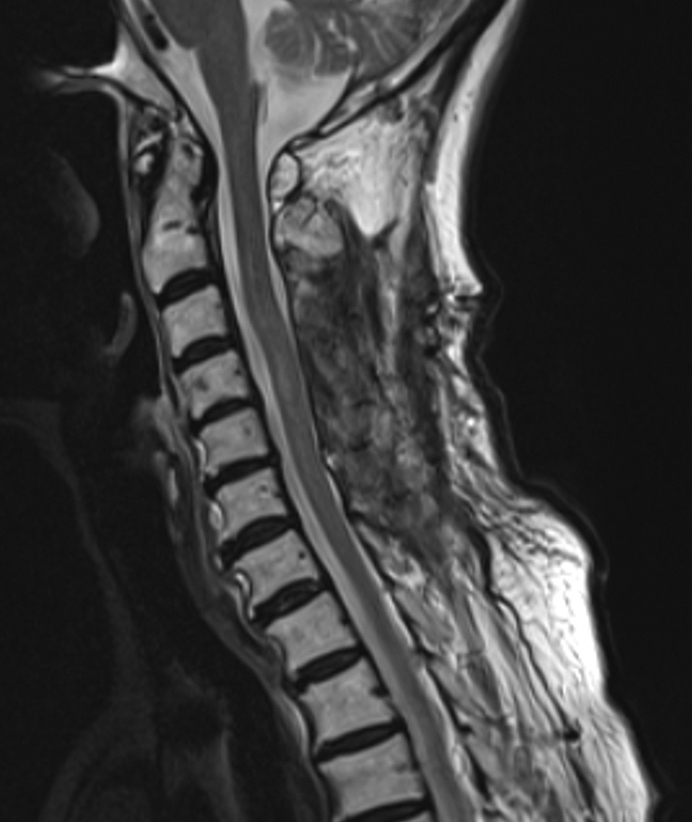

髓内脊髓脓肿很少引起意识受损而不引起颅内感染。我们报告的情况下,65岁的妇女谁提出颈部疼痛和右上肢无力。入院三天内,她的意识迅速恶化。最初的磁共振成像显示右侧C4-C5髓内病变,周围水肿延伸至脑干。脑成像未见异常。初步诊断为脊髓肿瘤。随访影像学显示病灶扩大伴环形强化。患者随后出现意识受损和四肢瘫痪。急诊手术发现并排出脊髓脓肿,培养物生长α-溶血性链球菌。手术后病人的意识恢复得很快。入院时发现先前未确诊的2型糖尿病。经广泛调查,未发现明显传染源。氨苄西林抗生素治疗持续1个月。两个月后的影像学显示脓肿完全消退。患者康复后恢复独立行走能力,仅残留轻微右臂无力。随访10年未见复发。本病例表明,颈脊髓脓肿可通过脑干水肿引起意识受损,而不发生颅内感染。早期手术干预配合适当的抗生素治疗可获得良好的结果。

Intramedullary spinal cord abscesses rarely cause impaired consciousness without intracranial infection. We report the case of a 65-year-old woman who presented with neck pain and right upper limb weakness. She developed rapidly progressive impaired consciousness within three days of admission. Initial magnetic resonance imaging revealed a right-sided intramedullary lesion at C4-C5 with surrounding edema extending to the brainstem. Brain imaging showed no abnormalities. An initial diagnosis of a spinal cord tumor was made. Follow-up imaging demonstrated lesion expansion with ring enhancement. The patient subsequently developed impaired consciousness and quadriplegia. Emergency surgery revealed and drained a spinal cord abscess, with cultures growing α-hemolytic Streptococcus. The patient's consciousness improved quickly after surgery. Previously undiagnosed type 2 diabetes was identified during admission. Despite extensive investigation, no obvious source of infection was found. Antibiotic therapy with ampicillin was continued for one month. Imaging at two months showed complete resolution of the abscess. The patient regained independent walking ability after rehabilitation, with only slight residual right arm weakness. No recurrence was observed during ten years of follow-up. This case demonstrates that a cervical spinal cord abscess can cause impaired consciousness through brainstem edema without intracranial infection. Early surgical intervention combined with appropriate antibiotics may lead to favorable outcomes.